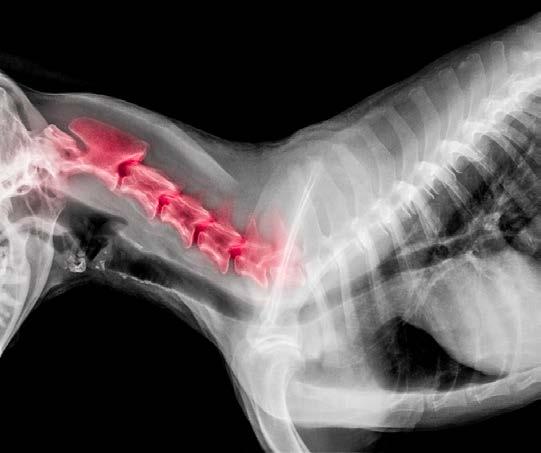

Osteoarthritis (OA) is one of the most common chronic conditions in dogs, and one of the most misunderstood. Many owners attribute stiffness, slowing down or irritability to ‘just getting old,’ when in reality these are signs of pain. Until recently, canine OA treatment options focused mainly on nonsteroidal anti-inflammatory drugs (NSAIDs), joint supplements, weight management and physiotherapy.

But the release of Librella®️ (bedinvetmab) has introduced an entirely new class of pain relief: one that is long-acting, targeted, and specifically designed for chronic arthritis in dogs. If your dog has OA or is showing early signs, this medication may be part of the future of comfort-focused care.

Senior dog behaviour changes

THAT SHOULD NOT BE IGNORED

As dogs grow older, subtle shifts in behaviour can feel easy to dismiss: a little more sleep, a touch of grumpiness, or moments of seeming ‘stubbornness.’ But ageing is not a disease and meaningful changes in behaviour are often your dog’s way of telling you that something deeper is happening. Early recognition makes an enormous difference to quality of life. Here are the senior-dog behaviour changes that should never be ignored, and what they may be signalling.

7. DECLINING MOBILITY, OR SUDDEN SLOWING DOWN

A dog who struggles to rise, hesitates on stairs, stops jumping onto furniture, or tires on walks is not just ‘getting old.’

Possible causes:

• Arthritis

• Muscle loss

• Spinal pain

• Neurological conditions

What to do: Early pain management is crucial. Joint supplements, anti-inflammatory medication, physiotherapy, and strengthening exercises can dramatically improve quality of life.